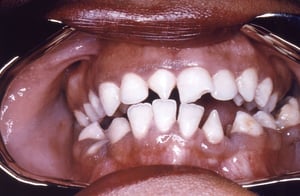

Hutchinson Incisors

This photo shows triangular shaped deformity of right upper and left lower incisors caused by congenital syphilis.

Image courtesy of Robert E. Sumpter via the Public Health Image Library of the Centers for Disease Control and Prevention.

Hutchinson incisors, mulberry molars, perioral fissures (rhagades), and maldevelopment of the maxilla resulting in “bulldog” facies are characteristic, if infrequent, sequelae.